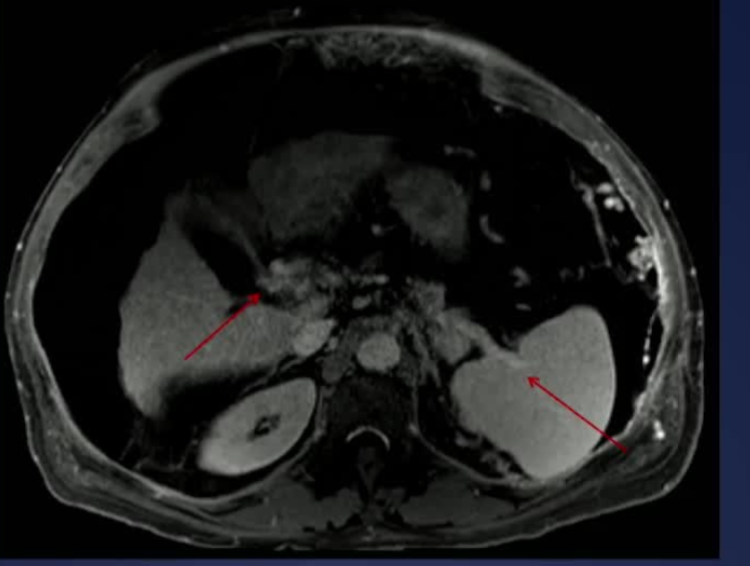

50岁 男性, 外科医生,25 年前的 PVT;目前胸水,工作繁重,生活受限,每周一次胸水引流,由于慢性肺静脉血栓形成而进行的移植手术

步骤: 鉴于慢性血栓形成的复杂性: 一种经脾脏途径的门静脉再通术(PVR)。 随后是经颈静脉肝内门体分流术 。

结果:术后影像学检查显示门静脉和脾静脉的血流情况有所改善,且残留血栓极少。